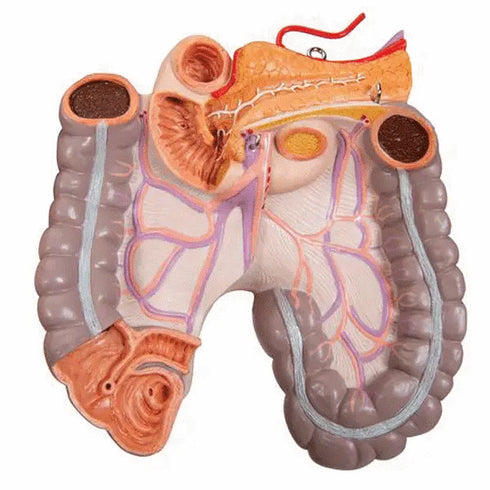

- tract intestinal (4 parti);